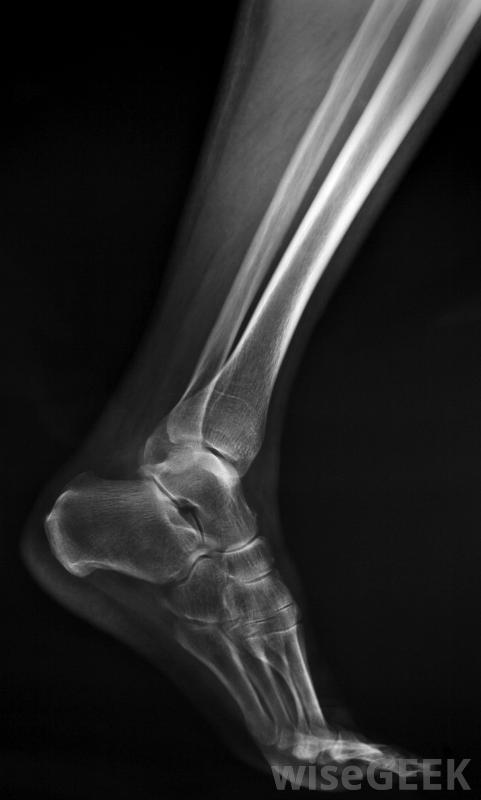

RICE代表休息、冰敷、加壓和抬高。如果骨折不嚴重,醫生可能會推薦這種方法來促進愈合,防止腫脹和疼痛。腓骨應力性骨折很可能是用這種方法治療的。x光片很可能是腓骨骨折治療的一部分,這一步對于確定損傷的嚴重程度非常重要。嚴重程度通常決定最好的治療方法腓骨骨折治療。如果骨折嚴重到皮膚破裂并引起劇烈疼痛或出血,腓骨骨折的治療將更加深入。

X光可以幫助確定腓骨骨折的嚴重程度。